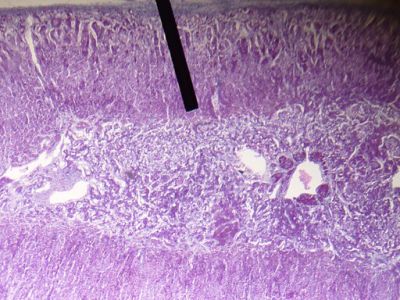

This is a histology slide of the adrenal gland. The pointer is on the zona reticularis of the adrenal cortex.

Image by Jpogi, via Wikimedia Commons. Public domain.

No changes were made to the original image downloaded (note: this version was downloaded at reduced resolution from Wikimedia Commons).